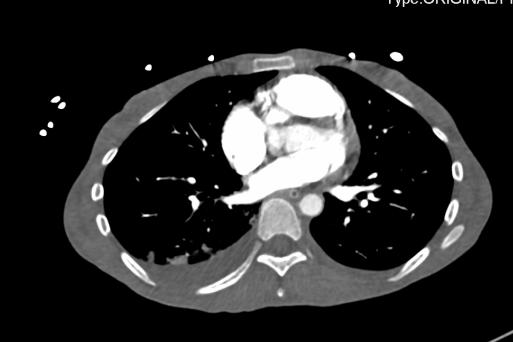

2021-4-29 CTPA:肺动脉干、左右肺动脉及其分支未见狭窄及明显充盈缺损。右肺、左肺下叶见斑片影、磨玻璃影及实变影。

2021-4-29全腹增强CT:腹盆腔散在积液,上腹腔少量积气,腹壁软组织积气,盆腔置管影。肝实质灌注不均,肝内淋巴瘀滞,提示肝功能损害。右侧见一支副肾动脉;左肾动脉提前分支。双侧附件区见多房囊状低密度影,可见环状强化,囊肿?卵泡?或其它?

患者青年女性,慢性病程;主要表现为腹胀、呼吸困难,术后出现意识障碍、II型呼吸衰竭。经呼吸机辅助呼吸、对症支持等治疗后,患者意识恢复但呼吸困难无明显改善;既往有有粉尘接触史。查体见患者极度消瘦、营养不良,双肺呼吸音粗,可闻及散在湿啰音。血气示II型呼吸衰竭、高碳酸血症,轻度贫血,低蛋白血症,电解质紊乱,炎症指标、肌酶、BNP升高,院外腹水检查示漏出液,未见肿瘤细胞;胸部CT:双肺斑片影,抗感染治疗后病灶吸收;腹部增强CT:双侧附件区分别混杂密度团块影,内见多发囊泡影;心脏彩超:右心稍大,重度肺动脉高压。